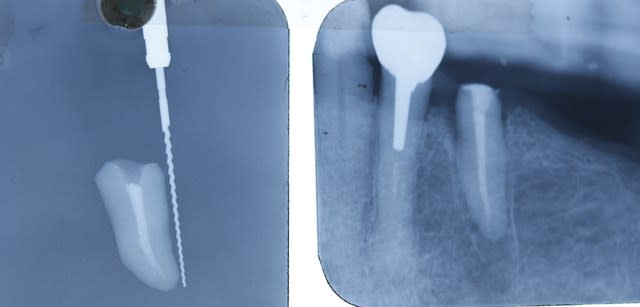

voilà des nouvelles du dernier cas .

je me suis trompé ,je ne l'ai pas enlevé debut janvier mais le 12 fevrier . on est donc à 1 mois

aujoud'hui , il n'y a pas de douleur ,la dent bouge un peu ( comme les autres dents ),il n'y a plus eu d' abces purulent .

la sonde paro rentre en distal .

la cale en occluson est tjs là , la dent n'etant pas collée à la canine .

la patiente est ravie , mais moi je le sens moyen ce coup !

ç est bien beau de la garder cette dent , mais pour en faire quoi ? ç est un plan à la con :-)

ce qui n'empeche qu'elle est tjs là , et on se demande bien pourquoi :-)).

Je l'ai indiqué par des flèches la lyse osseuse.

Si ça marche si bien et que c'est si simple, pourquoi cette technique est si peu décrite ?

" Je l'ai indiqué par des flèches la lyse osseuse. "

où ça Chatondecarte ?